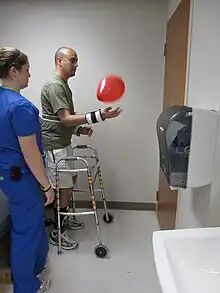

Rehabilitación

Se requiere de un programa de rehabilitación interdisciplinaria que provea una asistencia integrada para las personas que han sobrevivido a un ataque cerebral. Esta debe atender tanto los aspectos motores como los relacionados con el habla, los trastornos visuales, las actividades de la vida diaria y las secuelas incapacitantes como la espasticidad, para que el sobreviviente de un ataque pueda alcanzar un grado de independencia suficiente como para retomar, al menos parcialmente, sus actividades habituales. Este equipo interdisciplinar debe estar formado por fisioterapeutas, neuropsicólogos, fonoaudiólogos (logopedas), terapeutas ocupacionales y todos aquellos relacionados con la medicina, como el médico rehabilitador o fisiatra, el psiquiatra y el neurólogo.[49]

Una revisión sistemática de 15 estudios, la mayoría realizados en Asia, particularmente China, y uno en Sudáfrica, encontró evidencia de que la rehabilitación comunitaria genera un impacto positivo en personas con discapacidades. De seis estudios centrados en personas con discapacidades físicas, tres mostraron efectos beneficiosos para casos de apoplejía. Actualmente, nuevos ensayos clínicos tratan de esclarecer los beneficios cognitivos y emocionales de intervenciones basadas en mindfulness y ejercicio físico en la fase crónica del ictus.[50] Adicionalmente, resulta necesaria una evaluación de costo-efectividad de las rehabilitaciones que permita evaluar la asignación de los recursos.[51]